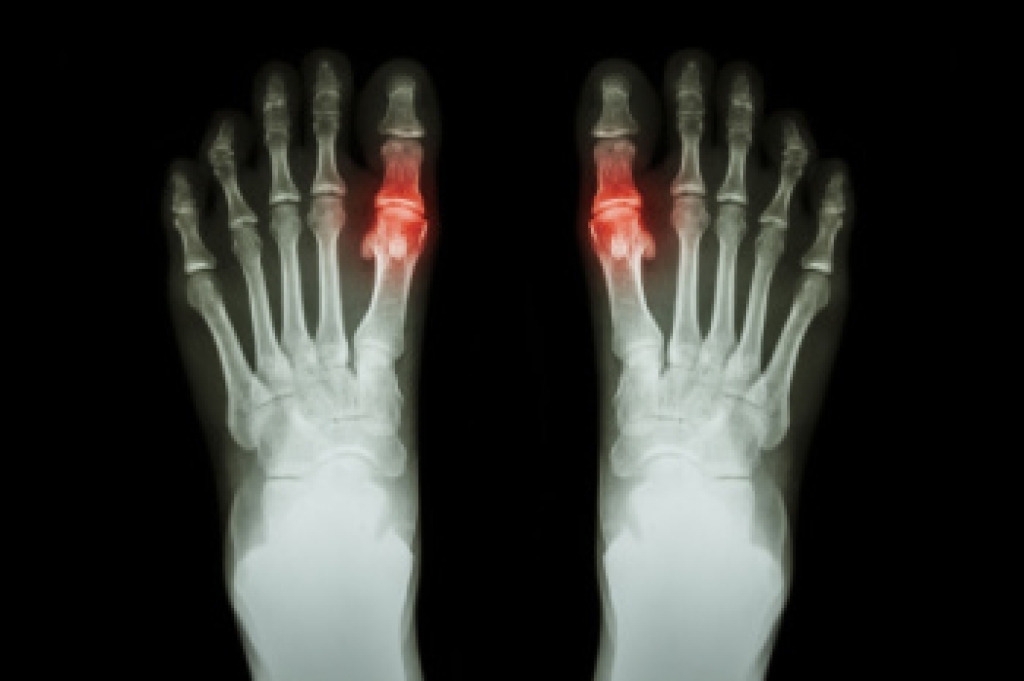

A broken ankle

Hammertoe surgery